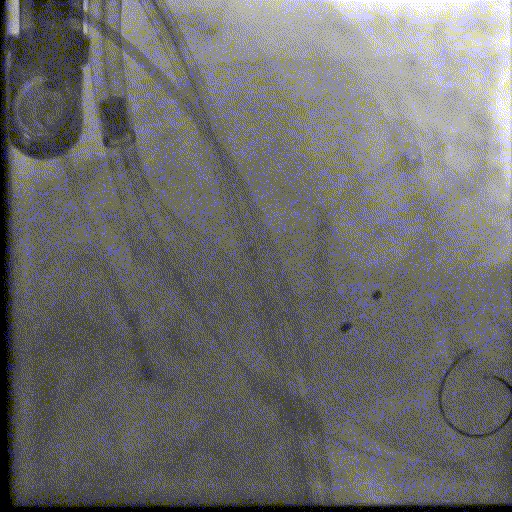

右侧股动脉入路检查

左侧股动脉入路检查

瓣膜形态

微量瓣周漏

植入后造影微量反流,超声提示瓣膜工作良好,最大跨瓣流速1.7m/s,平均跨瓣压差几乎为0,造影检查主入路,血管未见损伤,手术顺利结束。